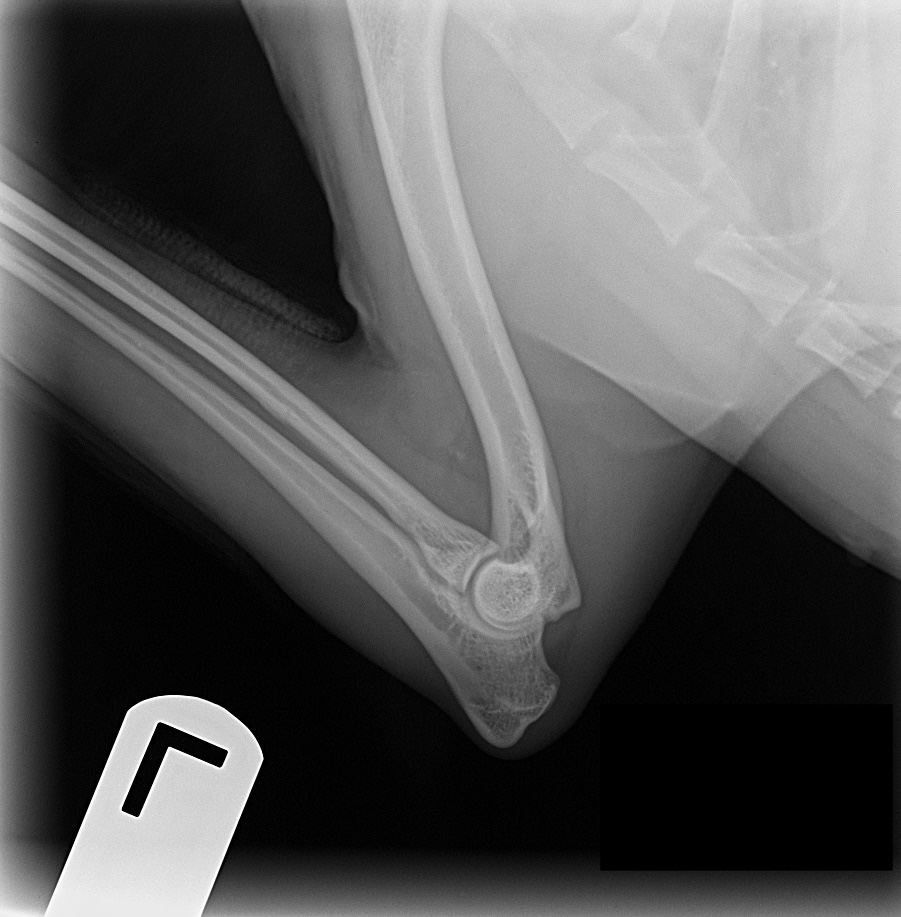

ofa | elbow

rating | normal